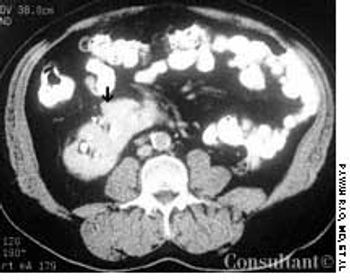

Frequent urinary tract infections and unexplained hypertension (160/100 mm Hg) occurred in a 38-year-old man with no significant medical history. The heart and chest were normal; a right lower quadrant mass was detected in the abdomen. Red blood cells were found in the urine. An abdominal CT scan demonstrated that the left kidney was fused to the lower pole of the right kidney with the left pelvicaliceal system to the left of the midline; these findings are consistent with crossed fused renal ectopia. Cystographic and cystoscopic examinations were normal.